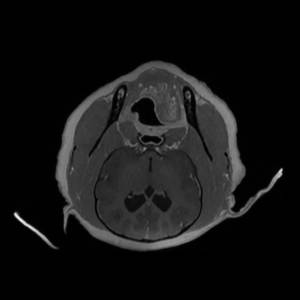

Main Gallery

Playing with a photo gallery function. It is possible to have multiple galleries, each within a namespace.